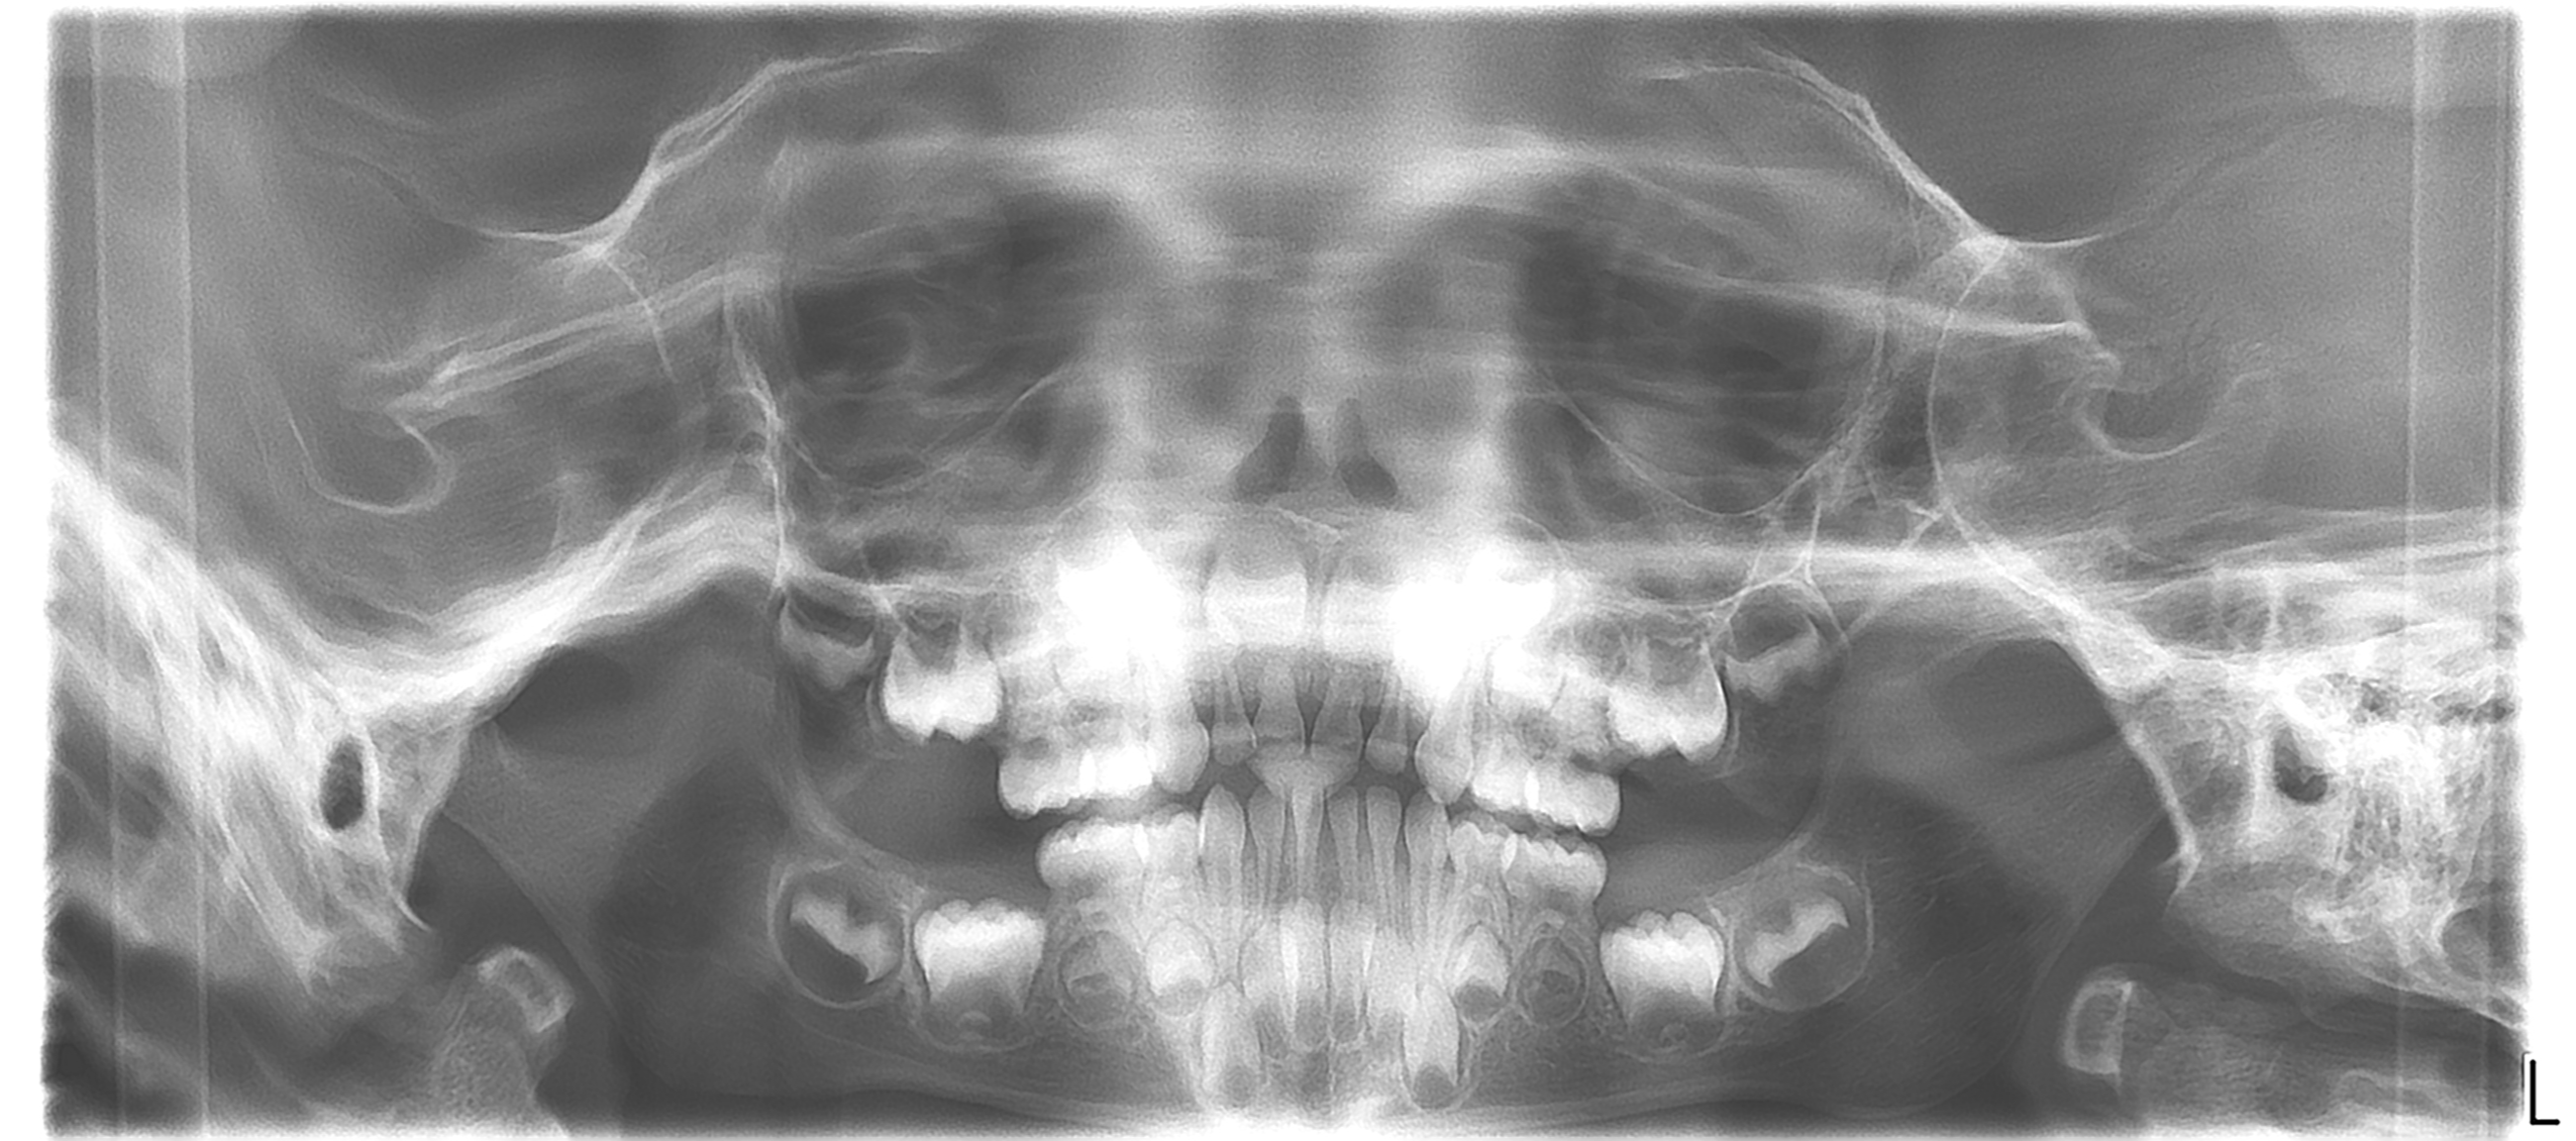

bilan des radiographies début et en cours de traitement